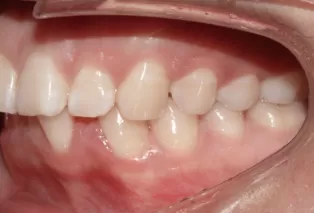

Femme, 25 ans. Plainte principale: dents saillantes et mal alignées, nécessitant un traitement orthodontique.

Ajustez les relations molaires gauche et droite par la distalisation simultanée des molaires supérieures et inférieures. Aligner la dentition en rétractant les dents antérieures. Avancez la mandibule pour améliorer le profil et le sourire gommeux.

Photos intra-orales